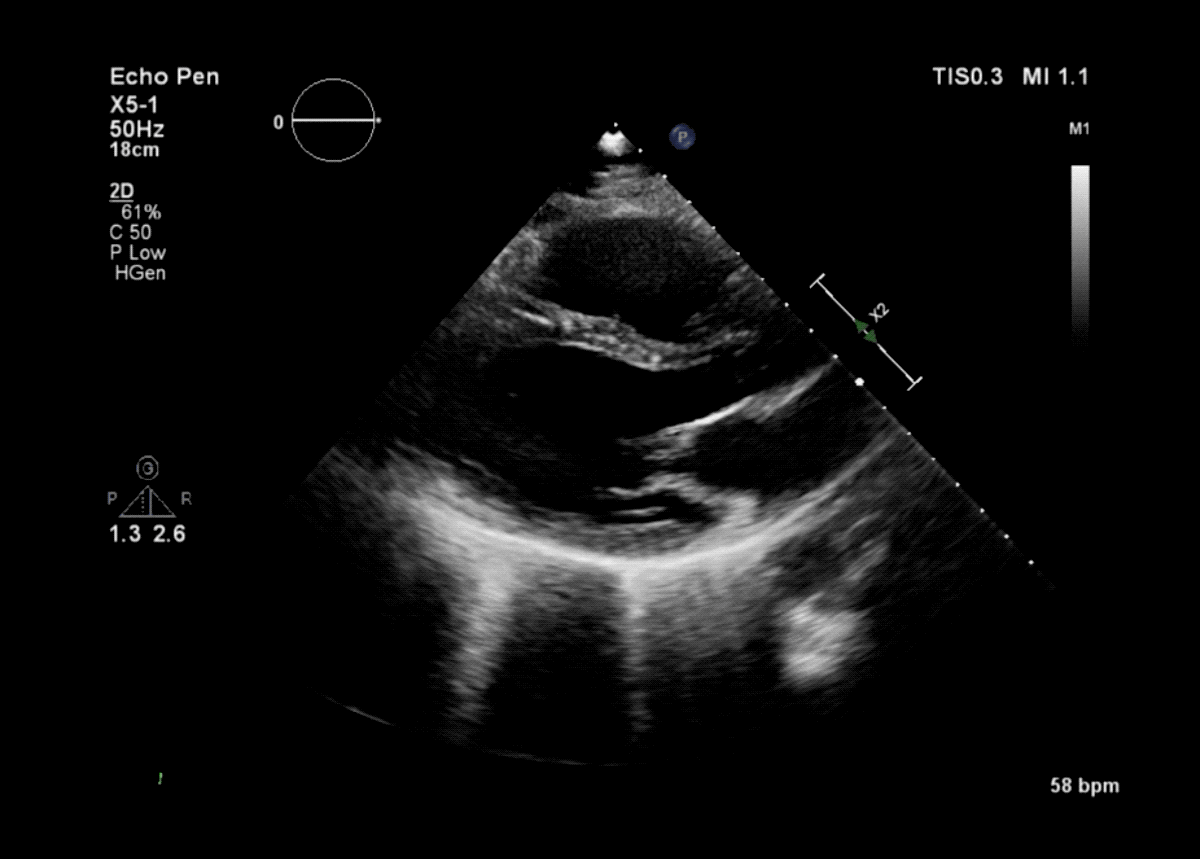

Healthcare startup Lyfebin exposed thousands of medical imaging files, such as X-rays, MRI scans and ultrasounds.

The storage bucket contained more than 93,000 files — many appeared to be duplicates — containing medical scans. The files were stored in the DICOM format, a common file type used by medical imaging equipment. When opened, DICOM files contain the images from the scan as well as other metadata, such as the patient’s date of birth and the name of the physician.